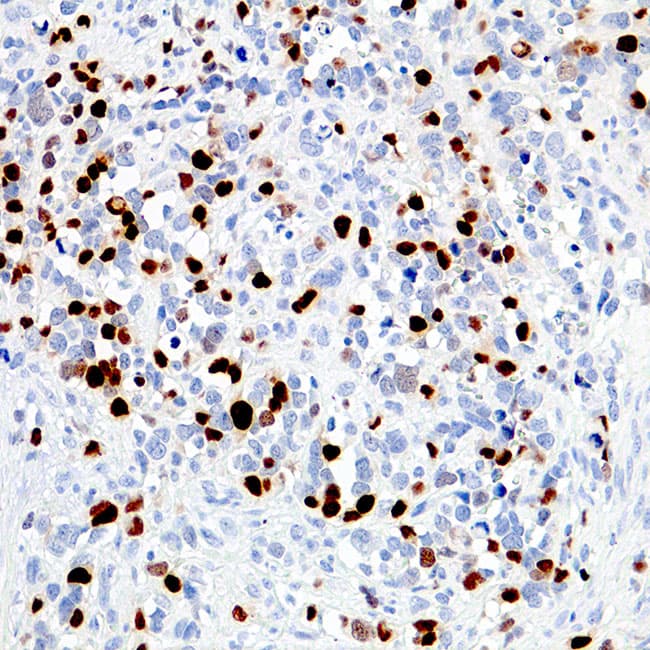

A miogenina pertence a uma família de factores de transcrição miogénica, incluindo MyoD, myf5, e MRF4, que são críticos no desenvolvimento muscular. Os factores miogénicos são factores de transcrição constituídos por uma região rica em aminoácidos e uma estrutura de hélice helix-loop-helix (HLH), que podem promover o desenvolvimento muscular e manter a expressão genética específica do músculo através da transativação. A miogenina desempenha um papel fundamental na determinação do compromisso e diferenciação das células mesenquimais primitivas em músculo esquelético. A miogenina é encontrada estritamente em células de origem do músculo esquelético, sendo por isso utilizada como biomarcador para tumores da linhagem muscular, incluindo rabdomiossarcomas alveolares. A coloração anti-Myogenin pode ocorrer no tumor de Wilms, e rotula os núcleos dos miooblastos no desenvolvimento do tecido muscular. É também expressa em alguns leiomiossarcomas.

Secção de rabdomiossarcomas